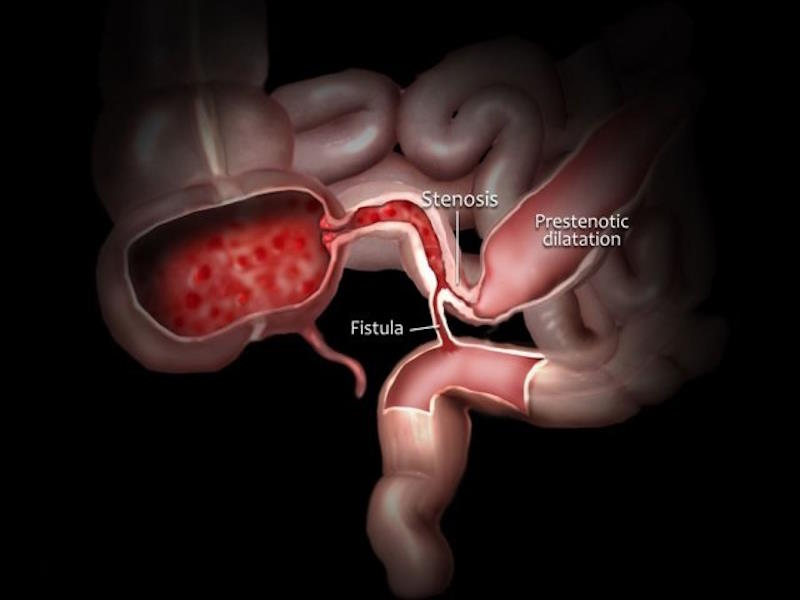

Crohn's disease

Crohn's disease Community awareness